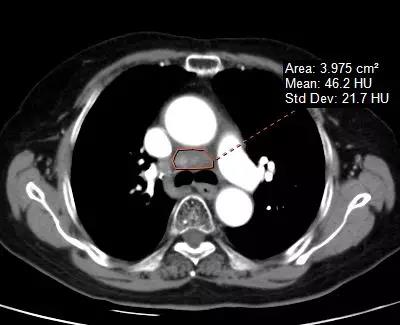

▲ 纵膈占位伽玛刀治疗前和伽玛刀治疗后对比,肿块明显缩小,压迫症状好转